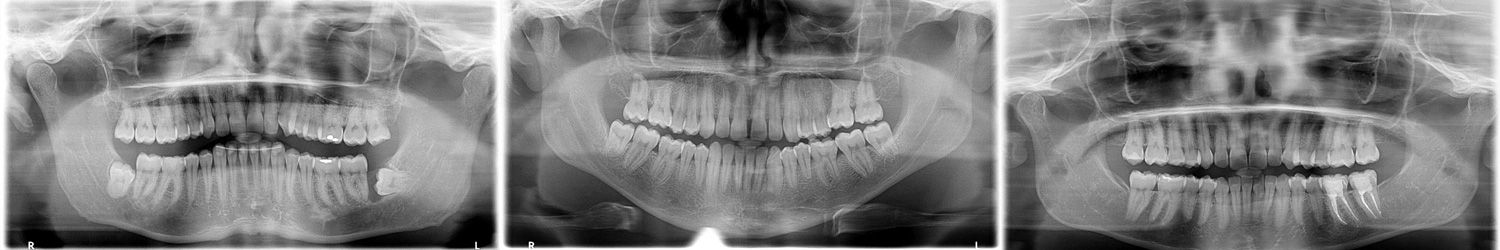

Zu den technischen Möglichkeiten unserer Praxis gehören neben herkömmlichen Detail- und Panorama-Röntgenaufnahmen auch die moderne digitale Volumentomographie. Das auch als digitales 3D-Röntgen bekannte Verfahren ist fortschrittliche Röntgentechnik, mit der wir hochauflösende dreidimensionale Aufnahmen aller Strukturen im Mund- und Kieferbereich anfertigen, in Minutenschnelle digitalisieren und am Computermonitor von allen Seiten betrachten können. Damit verfügen wir über ideale diagnostische Möglichkeiten und hervorragende Voraussetzungen für die Planung von Behandlungen.

So können wir uns im Vorfeld einer Wurzelkanalbehandlung ein klares Bild von Anzahl und Verlauf der Wurzelkanäle eines Zahns machen. Vor schwierigen Weisheitszahn-Extraktionen sind wir in der Lage, die anatomischen Verhältnisse im Kiefer, wie etwa den Verlauf von Nerven, zuverlässig zu beurteilen.

Bei der Planung von Implantationen können wir anhand von 3D-Aufnahmen die Breite und Höhe des Kieferknochens exakt vermessen und damit verlässliche Prognosen für Aufwand und Dauer der Behandlung abgeben. Digitales 3D-Röntgen ist eine günstigere, weniger aufwändige und gerade in der Zahnmedizin in vieler Hinsicht sogar überlegene Alternative zur Computertomographie. Einer ihrer aus Patientensicht wichtigsten Vorteile ist die bedeutend geringere Strahlenbelastung durch erheblich schnelleres Arbeiten mit dem fokussierten Röntgenkegel. Ein weiteres Plus: der Servicevorteil. Wir müssen Sie nicht an ein Röntgeninstitut überweisen, sondern führen die gesamte Diagnostik hier in der Ordination durch. Sie sparen sich zusätzliche Wege und Wartezeiten.